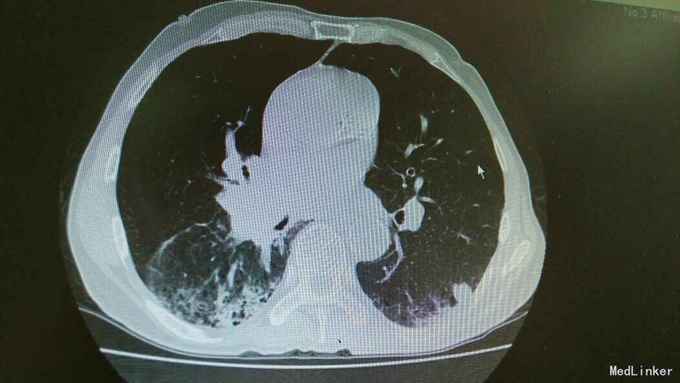

主诉:活动后气促,胸闷1年,消瘦8月余。 病史:患者1年前无明显诱因出现活动后气促,胸闷,主要为胸骨段,爬坡可诱发,伴有咳嗽,白色粘痰。伴有体重下降。

查体:慢性病容,桶状胸,双肺呼吸音粗,右下肺可闻及少量细湿罗音。 辅查:胸部CT:考虑右下肺中央型肺癌并癌性空洞形成,右下肺阻塞性肺炎 ,右下肺动静脉受累,纵隔,双侧肺门多发淋巴结肿大。

诊断:中央型肺癌并阻塞性肺炎。 治疗:入院予以抗感染,止咳化痰等治疗。

随访+讨论:患者肺癌已经为晚期,失去治疗时机,目前只能予以抗感染及对症处理。